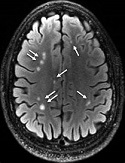

Several doctors have explained that the MRI or Magnetic resonance imaging is the Holy Grail for patients with multiple sclerosis. Most doctors prescribe an MRI once yearly to search for new lesions showing the possible progression of MS. However, my doctor in Ohio, Dr. Connor, only prescribes an MRI when something significant occurs, as instructed by his mentor. That being the case, since my diagnosis twenty-two years ago, I have had fewer MRIs than the average MSer, with no new lesions in eighteen years.

My Floridian neurologist, Dr. Fein, wanted me to get an updated MRI to look for new lesions; my last MRI spot was nearly two decades ago. Unfortunately, Dr. Fein is just over an hour away, yet thankfully we can perform the MRI much closer to home. When scheduling the MRI, they told me it should take ninety minutes, but I should plan for two hours just in case. So I booked the magnetic photography session as soon as possible, four months, two weeks, and three days after the phone call. I kept reminding myself that time moves quickly and would be here before I knew it.

After nearly two hours, we were halfway through the scans when Jim stopped the machine. He offered me the option to leave and return on another day to finish the second half of the scans. My reply was, “I’m game to stay if you are. I’m here now, so why not just keep going? Besides, it has to be better for you to get everything done at once.” So, with the continuous jumping of my legs, we resumed the second half of the scans, which took an additional ninety minutes. Jim explained how the Charleston dance-style leg movements shook my head and body, making the scans somewhat blurry.